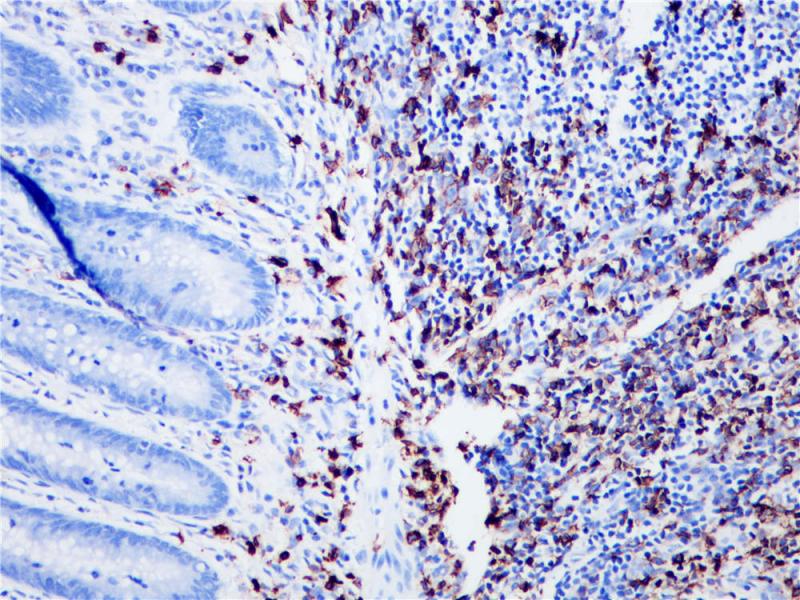

CD20是一种膜内嵌的非糖基磷酸化蛋白分子,分子量约为33kDa,在B细胞活化、分化和增殖中起重要的调节作用。CD20抗原是一种B细胞分化抗原,临床应用为诊断识别B系非霍奇金淋巴瘤(NHL),还可帮助诊断结节性淋巴细胞优势型霍奇金淋巴瘤和急性淋巴细胞瘤。

阳性对照

扁桃体

亚细胞定位